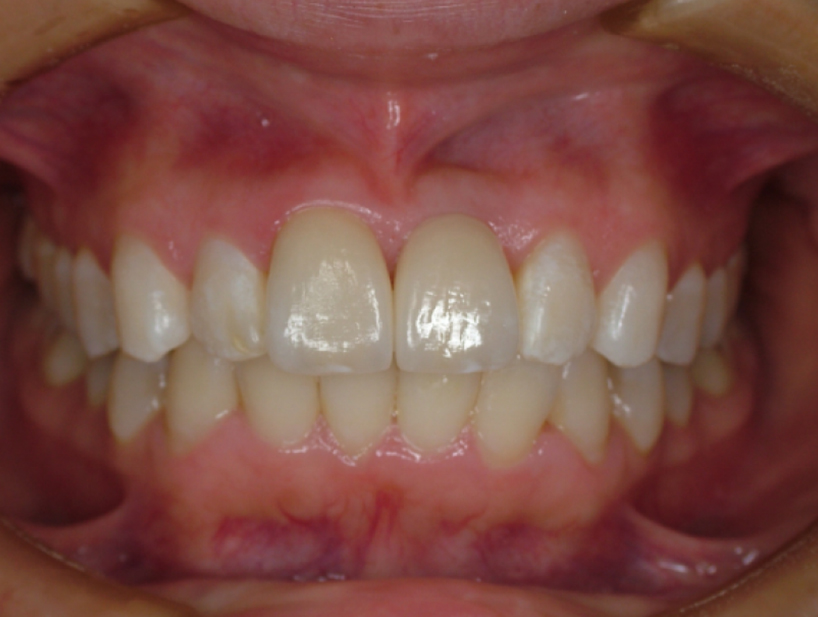

治療前治療後

| 治療内容 | インプラント奥歯1本・根管治療6歯 |

|---|---|

| 患者様の年齢 | 54歳 |

| 患者様の性別 | 女性 |

| 治療期間 | 2年 |

| 治療回数 | 根管治療合わせて70回程度 |

| 治療費用 | インプラント1歯 50万円/根管治療6歯 30万円 |

| 治療で得られるメリット |

|

| 治療する際に起こる リスク・副作用 |